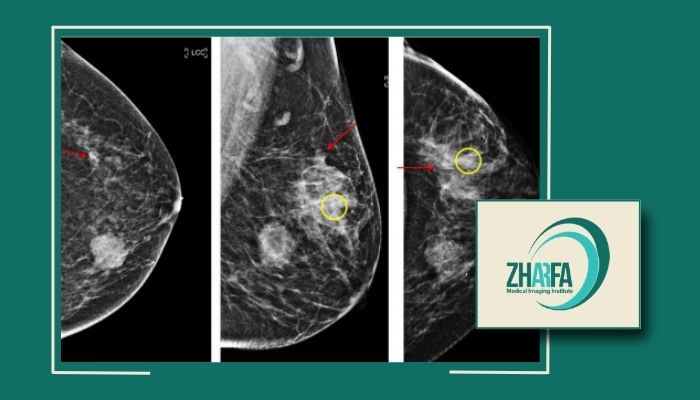

در مرکز ژرفا از تکنولوژیهای نوین و پیشرفته مانند رادیوگرافی دیجیتال و سونوگرافی استفاده میشود که امکان تشخیص دقیق و زودهنگام بیماریها را فراهم میآورد. این تجهیزات پیشرفته بهویژه برای شناسایی بیماریها در مراحل اولیه و تودههای کوچک بسیار مؤثر هستند و به پزشکان کمک میکنند تا تصاویر واضح و دقیق از ساختارهای داخلی بدن دریافت کنند.